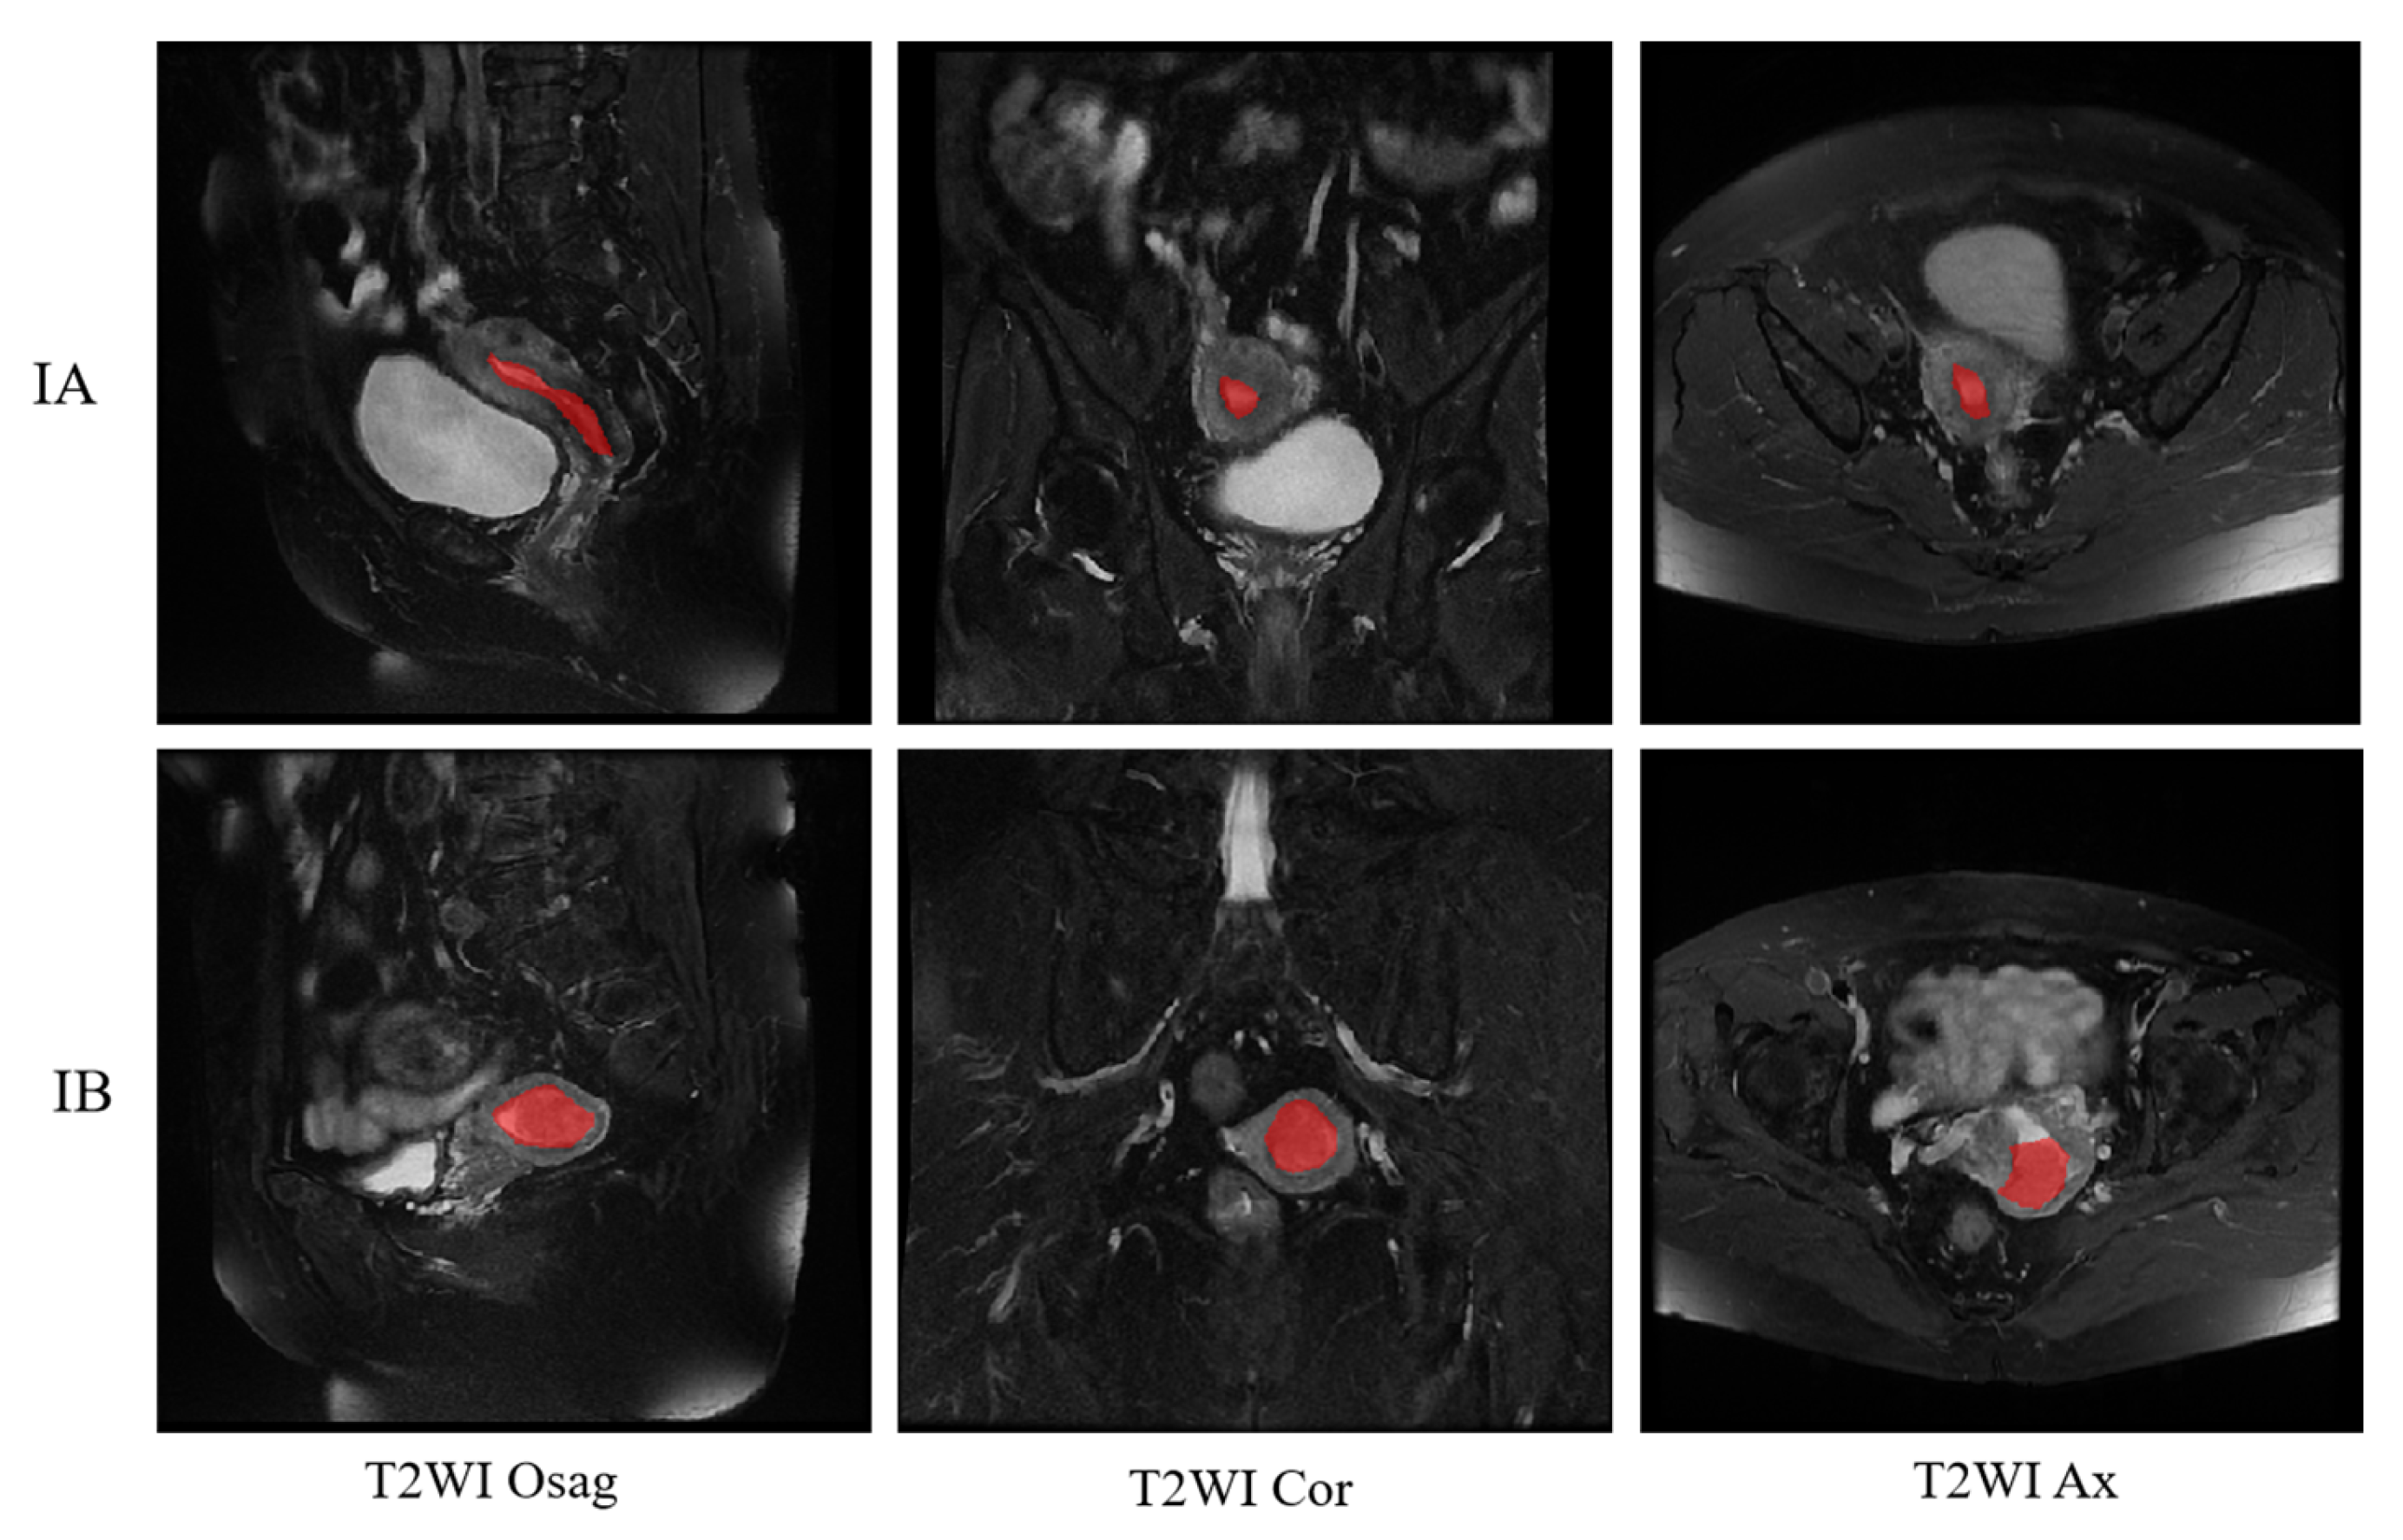

Figure 10 shows the final staging results. The upper side shows the segmentation image of the three positions of T2WI of a patient with stage IA, and the lower side shows the segmentation of the three positions of a patient with stage IB, where the red is the region of cancer foci. The segmentation image shows that the model correctly recognizes the cancerous areas of the three body positions.

Figure 10. Classification results of T2WI for stage IA and IB. The red represents the cancerous area.